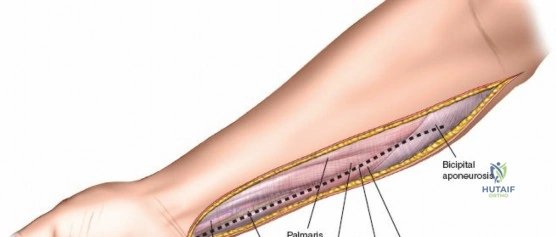

Incision: A curvilinear incision is made from the medial epicondyle, across the antecubital fossa, extending obliquely to the mid-volar aspect of the forearm, and then longitudinally down to the wrist crease, potentially extending into the palm to release the carpal tunnel. The incision should be generous, allowing for wide exposure.

- Key points: The proximal portion of the incision should curve gently to avoid crossing the elbow flexion crease at a right angle, which could lead to contracture. Distally, it should avoid cutting directly over the median nerve at the wrist.

This image shows the standard curvilinear incision for the volar approach, extending proximally from the medial epicondyle, gently crossing the antecubital fossa, and proceeding distally across the mid-forearm to the wrist.

- Key points: The proximal portion of the incision should curve gently to avoid crossing the elbow flexion crease at a right angle, which could lead to contracture. Distally, it should avoid cutting directly over the median nerve at the wrist.

Skin and Subcutaneous Tissue: Incise the skin and subcutaneous tissue. The superficial fascia is then identified.

This image depicts the initial incision through the skin and subcutaneous tissue, exposing the underlying superficial fascia. -

Release of Superficial Volar Compartment: The superficial investing fascia of the forearm is carefully incised longitudinally throughout the length of the exposure. This releases the pronator teres, FCR, palmaris longus, FCU, and FDS.

- Proximally: Identify and protect the median nerve as it passes between the two heads of the pronator teres. The superficial head of the pronator teres can be released to facilitate access to the deep compartment. The Lacertus Fibrosus (bicipital aponeurosis) should also be released as it can be a source of compression.

- Mid-forearm: The FDS muscle bellies are prominent. Ensure the fasciotomy extends across the full width of the compartment.

Here, the superficial volar fascia has been incised, demonstrating decompression of the superficial flexor muscles. Note the muscle bulging as pressure is released.